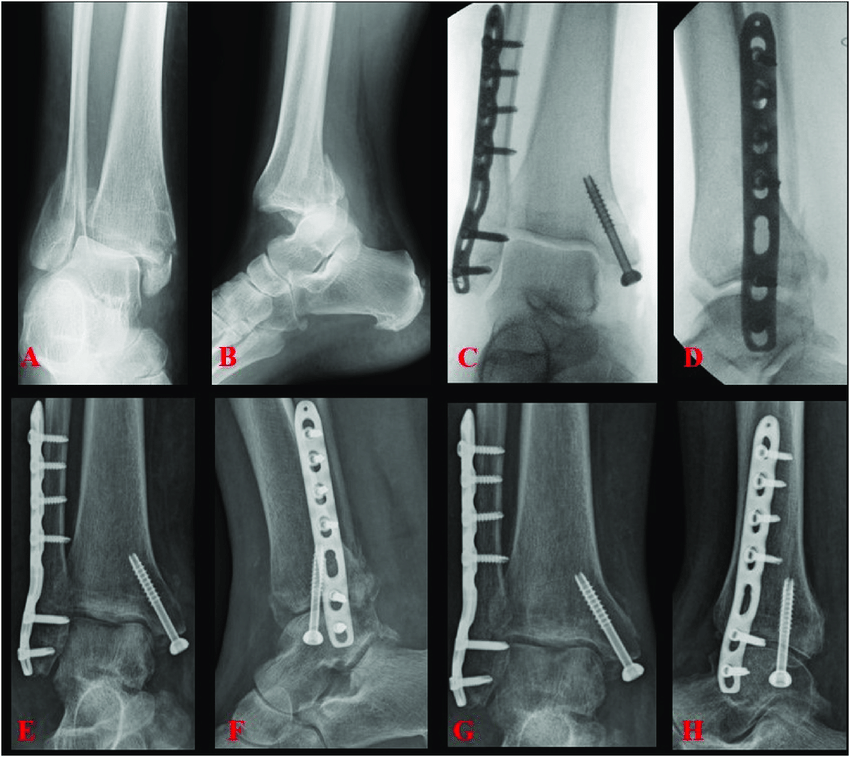

Trimalleoler kırık, ayak bileğinin üç malleolünün birlikte kırılmasıdır.

Kırıklı-çıkık dendiğinde buna ek olarak tibiotalar eklem çıkığı vardır. Bu nedenle instabil ve acil bir ortopedik durumdur.

ORIF (Açık redüksiyon + internal fiksasyon) neredeyse her zaman gerekir

Çıkık + trimalleoler kırık = cerrahi kaçınılmaz (istisnalar çok sınırlı)